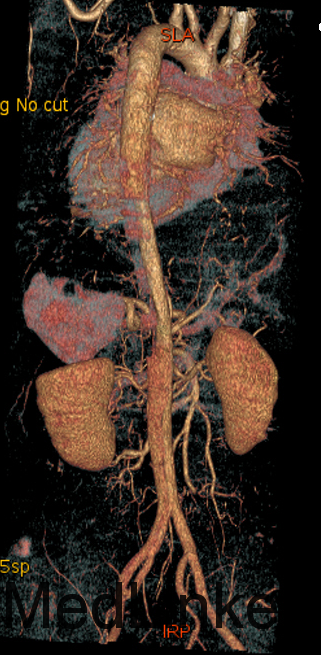

入院查体:体温36.5℃,脉搏90次/分,规则,呼吸18次/分,规则,血压150/80mmHg,胸廓正常,无胸骨叩痛。呼吸运动正常,语颤正常,无胸膜摩擦感,无皮下捻发感,叩诊正常清音,肺下界正常,双肺呼吸音粗,呼吸音对称,无罗音。心音可,心率90次/分,无杂音,腹部无压痛,无反跳痛,肝肋下未及,胆囊无压痛,Murphy征阴性,脾肋下未及,肾区无叩痛,双下肢不肿。入院后完善相关检查(胸腹主动脉CTA:主动脉夹层动脉瘤;两侧胸腔少量积液。)

予以诊断:1.主动脉夹层动脉瘤;2.高血压3级,极高危组。诊断明确后行“左颈总动脉-腋动脉转流手术+胸主动脉覆膜支架腔内隔绝术”。左侧颈部切口,游离出左侧颈总动脉,左侧锁骨下动脉,左侧椎动脉等分支。使用8mmG-tex血管一端与左锁骨下动脉行端侧吻合,G-tex血管另一端与左侧颈总动脉行端侧吻合。经右侧股动脉入路造影见主动脉夹层,破口位于左锁骨下动脉开口医院0.5cm处。左锁骨下动脉近端封闭,桥血管通畅,腋动脉及左侧椎动脉血流良好。置入美敦力胸主动脉覆膜支架(28*157mm),定位后释放。造影见胸主动脉支架释放良好。

主动脉夹层为大血管急诊,B型主动脉夹层相对预后良好。保守治疗效果尚可,近期死亡率相对不高。但对于年轻患者,我们积极治疗。患者B型主动脉夹层,破口位于锁骨下动脉附近。拟行腔内修复术。但患者破口离锁骨下动脉较近,若直接封闭,可影响左上肢活动及椎动脉顺行血流。故根据患者情况行一期复合手术(即“左颈总动脉-腋动脉转流手术+胸主动脉覆膜支架腔内隔绝术”)。术后复查可及左侧锁骨下动脉通畅,血流灌注可。可及假腔内明显血栓化。